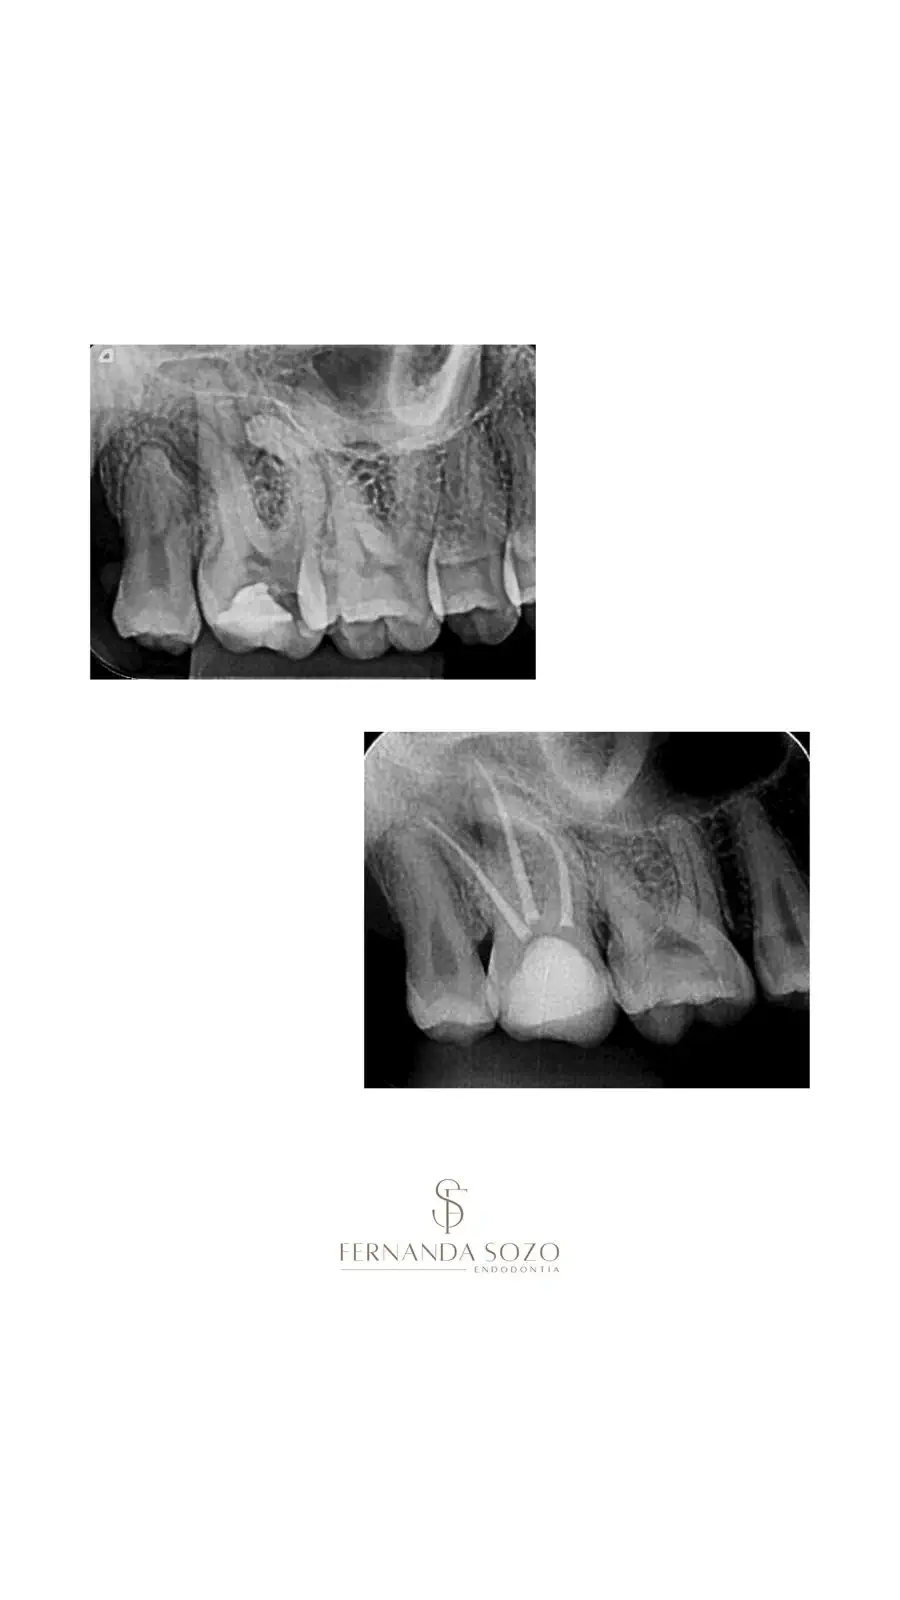

Portfólio

Casos Clínicos

Resultados que demonstram precisão técnica e excelência.